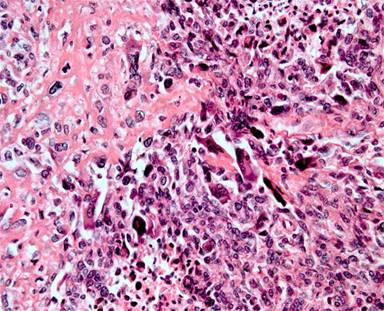

A sixty-six-year-old woman was admitted to our hospital who had suffered abdominal pain and nonspecific nausea for almost 40 days. Physical examination showed a vaguely palpable left upper abdominal mass with mild deep tenderness. Laboratory data including tumor marker (CA 19-9, CA 153, CEA, etc.) was normal. Abdominal ultrasound, magnetic resonance imaging (MRI) and computed tomography (CT) revealed a clear-bordered cystic–solid mass with heterogeneous density involving the tail of the pancreas (Figure 1). It measured approximately 4.0×5.0 cm, without any evidence of metastasis or invasion of the adjacent vessels and other tissues. We performed an en bloc distal pancreatectomy with splenectomy for radical excision, as well as regional lymphadenectomy. The postoperative pancreatic fistula and intra-abdominal abscess led to prolonged hospitalization (25 days), and was cured through percutaneous drainage and antibiotics. Gross examination revealed a 4.0×5.0 cm exophytic clear-bordered neoplasm of the tail of the pancreas containing necrotic and calcified areas, without invasion of the spleen (Figure 2). Three suspicious lymph nodes around the splenic artery and two around the splenic hilum were resected and evaluated for invasion. The lymph node involvement was not detected (0/5) and the surgical margins were negative (R0). The pathological examination revealed pleomorphism with giant cells and the spindle-shaped cells with anaplasia seen in hematoxylin and eosin (H&E) staining of tumor tissue (Figure 3). Immunohistochemical staining of tumor tissue was negative for smooth muscle actin (SMA), pancytokeratin (PCK), epithelial membrane antigen (EMA), S100, β-catenin and CD10, but weak positive for vimentin (Figure 4).

Figure 3. H&E stain with ×400 magnification, showing the presence of spindle-shaped cells with anaplasia and neoplastic giant cells. Neoplastic osteoblasts and irregular mitosis are seen. It is also showing a focal osteochondroid differentiation within the tumor. |

Additionally, the tumor contained a focal area of osteochondroid differentiation. According to the histological and immunohistochemical observations, a diagnosis of undifferentiated (spindle cell) carcinoma of the pancreas with focal osteochondroid differentiation was made.